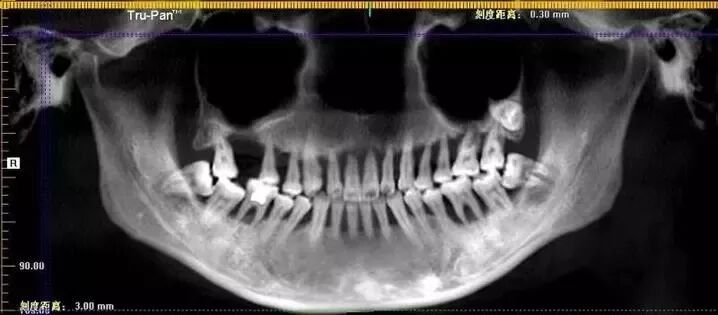

因刷牙时突然一颗门牙脱落,28岁的小萌(化名)到口腔机构就诊,医生告知她:由于牙周疾病一拖再拖,上排牙已经全部不能保留。

△牙片中清晰可见小萌的上口牙已摇摇欲坠